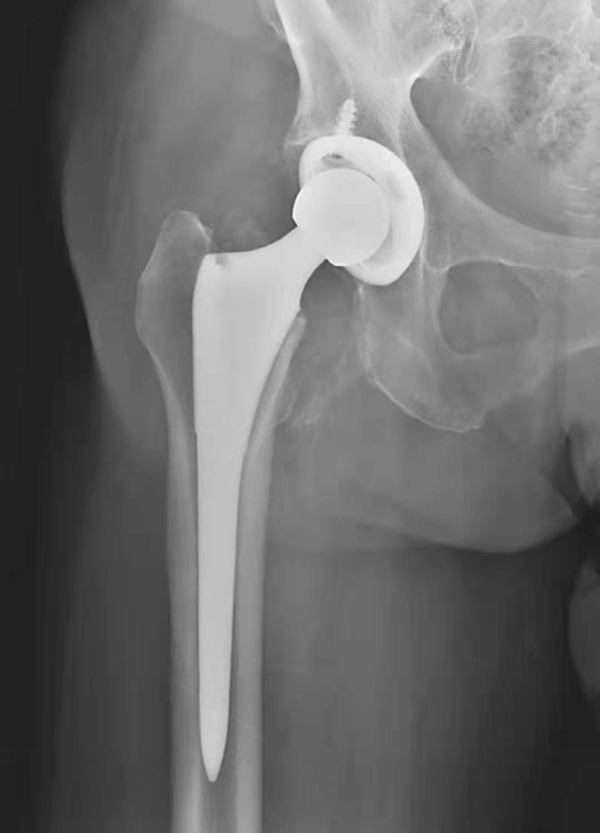

图6 右侧人工髋关节置换术后异位骨化

平片,右侧人工髋关节外方可见条片状骨化影

图7 右侧人工髋关节置换术后异位骨化

平片,右侧人工髋关节外上方可见条片状骨化影

图8 右侧人工髋关节置换术后异位骨化

平片,示右侧人工髋关节内下方见条片状骨化影